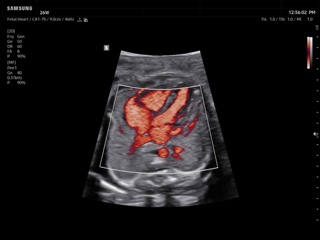

Atlas of ultrasound images - obsterics

In the section "Оbsterics" of atlas the results of ultrasonic examinations of pregnant women with different durations of gestation are represented. Here you can see images of internally organs, cerebrum, cordis and the sex of the fetus, the sonograms of multiple pregnancy, the blood flow in placenta and umbilical cord, defects of fetal`s development, etc.